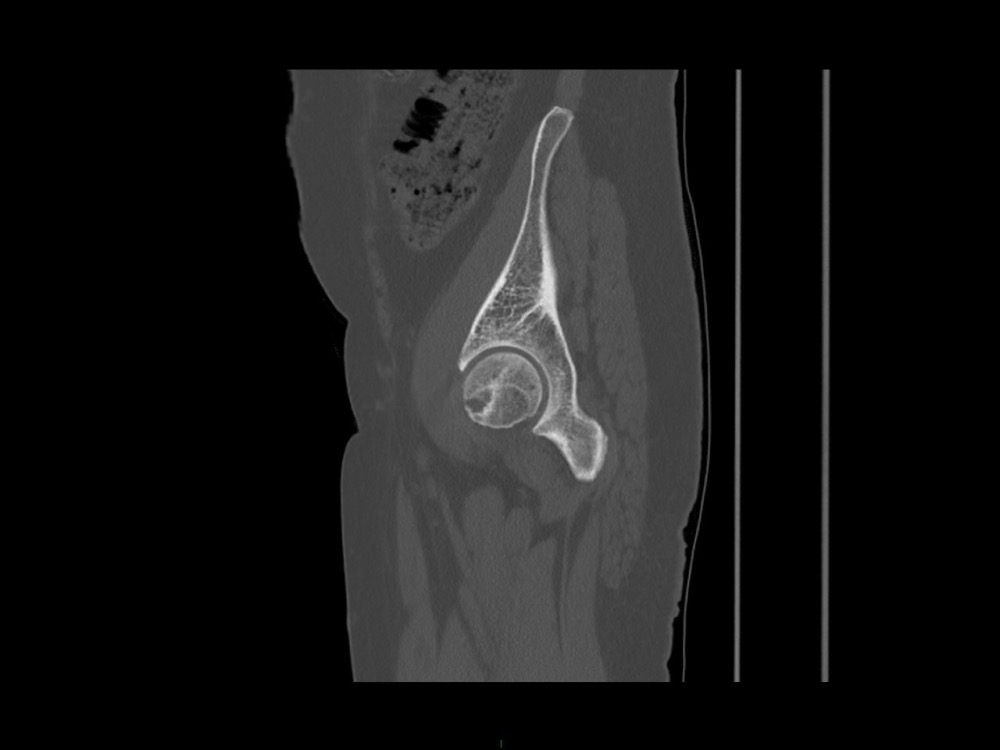

Aboudaram / Burns 11/01/2023